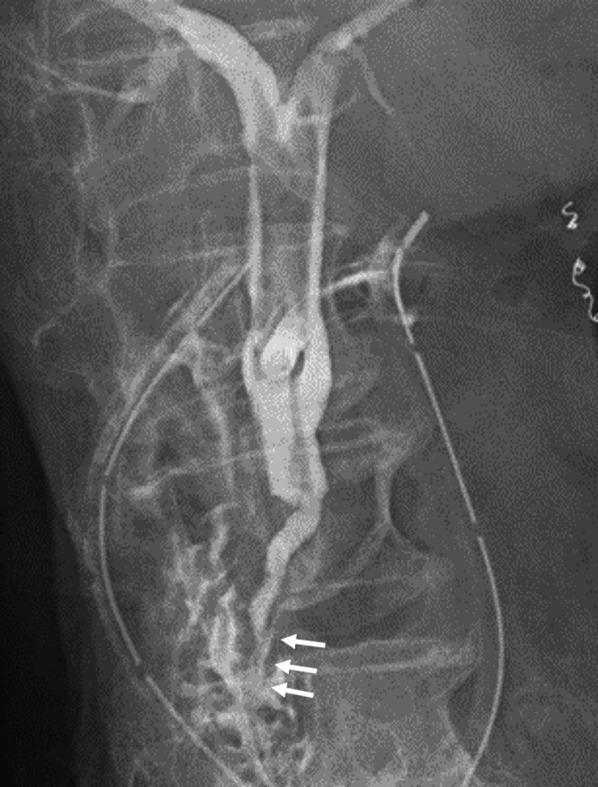

The patient remained unstable and required inotropic agents, artificial respirator support and continuous hemodiafiltration in the intensive care unit until postoperative day 10. Furthermore, multiple additional drainage, and administration of antibacterial and antifungal agents were required for the refractory intra-abdominal and retroperitoneal abscesses. On day 16, active bleeding was observed at the abdominal wall around the T-tube, and hemostasis was achieved by transcatheter arterial embolization. On day 55, T-tube cholangiography revealed that the impacting CBD stone had disappeared naturally and, thus, the long common channel of the pancreaticobiliary duct and the diagnosed pancreaticobiliary maljunction could be observed (Fig. 5). After removal of the T-tube on day 136, she was transferred to the hospital for recuperation on day 152.